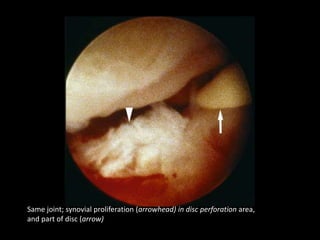

Upper joint compartment; synovial proliferation (arrowhead) in disc perforation

area,hyperemia (small arrowhead), and part of disc (arrow

Same joint; synovial proliferation (arrowhead) in disc perforation area,

and part of disc (arrow)